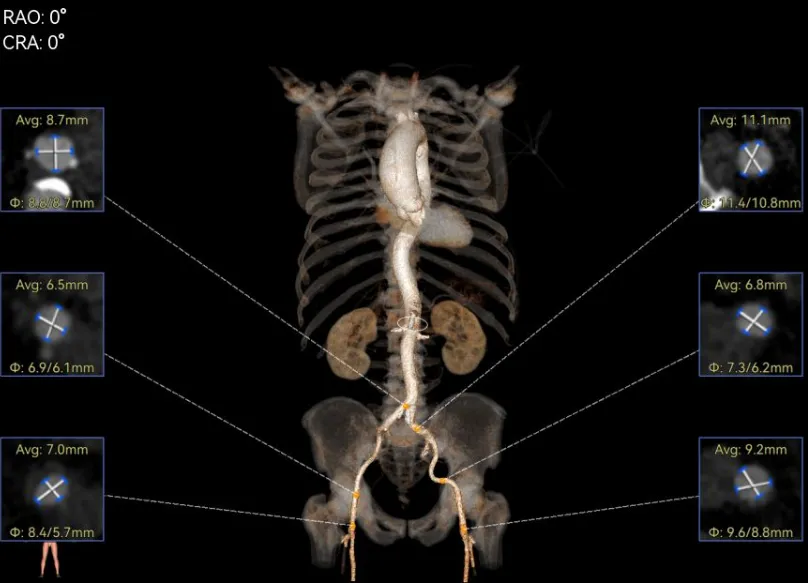

谷兴华教授 山东大学齐鲁医院 锚定终身获益,重视首次干预选择:心脏瓣膜病介入中心成立2年多来,中心核心目标始终保证在解决即刻病症的基础上,护航患者的全生命周期健康管理。 摆在眼前的实际是日益年轻化的患者群体,这意味着我们从手术伊始,就必须将患者未来数十年的生活质量和再次干预风险纳入核心考量,主动规划长远的健康路径。此次患者选择更具耐久的新型干瓣技术,力求减少患者未来再次干预的风险。同时,通过“TAVR+PCI一站式手术”这样的团队协作模式,系统性地处理多重心血管问题,避免分次手术的负担与风险,这正是我们中心一直秉持的“心脏瓣膜病全生命周期管理”理念的实践。让我们一起探索从“治已病”真正迈向“管长远”,让更多的患者获益! 病例特点速览 本次救治的患者,病情呈现“基础病交织、多病变叠加、锚定风险高”三大核心特征。患者为65岁,女性,病变特点TypeI型二叶瓣、轻度钙化,锚定风险大;同时患有冠状动脉粥样硬化性心脏病、慢阻肺(COPD);既往有长期吸烟饮酒史、脑梗死病史、高血压病史、乙肝小三阳病史及腹股沟疝修补手术史,患者STS评分9.32%,外科手术高危,经齐鲁医院瓣膜中心团队评估认为:局麻下“一站式TAVR+PCI”为最优治疗方案,结合患者较年轻,可选择具有长期耐久性的干瓣。 患者病史 主诉:活动后胸闷、憋喘余,加重20余天 既往史:30年前确诊乙肝小三阳,否认其他传染病史;有右腹股沟疝修补手术史,高血压病史,近期规律服药控制。 现病史:患者1年前出现活动后胸闷、憋喘,休息可缓解,为进一步诊治。2月前因“突发意识模糊、口齿不清”于当地医院入院,诊断为“急性脑梗死”,予以微创介入取栓治疗,恢复可,未遗留后遗症。20天前于当地医院再次入院行脑血管支架植入术,术后出现胸闷、憋喘,伴大汗,行心脏超声提示主动脉瓣重度狭窄,并行冠脉造影检查,予以药物治疗。10天前就诊于我院复查心脏超声提示二叶式主动脉瓣,主动脉瓣狭窄(重度)并反流(轻度)。患者现仍感胸闷,双上臂疼痛不适,咳嗽咳痰,日常活动受限。为行进一步治疗就诊于我院,门诊以“主动脉瓣狭窄、冠状动脉粥样硬化性心脏病”收入院; 个人史:吸烟50年,饮酒50年; 体格检查:体温:36℃,脉搏:67次/分,呼吸:18次/分,血压:143/76mmHg; 术前超声提示: 二叶式主动脉瓣主动脉瓣狭窄(重度)并反流(轻度);升主动脉扩张、左心扩大三尖瓣反流(少量);左室充盈异常;CW测最大压差86mmHg,平均压差43mmHg,最大血流速度463cm/s,连续方程法估测主动脉瓣口面积0.78cm² 术前CT评估 Type1型二叶瓣,轻度钙化、左右融合,主动脉瓣环径25.3mm,LVOT直径25.5mm,鱼嘴空间约26.6mm,主要靠瓣环锚定。窦部空间大、左右融合,VTC空间足够,无冠脉风险 ;左室内径正常,主动脉瓣环水平夹角49.6°。外周双侧入路内径可,髂外动脉存在散在钙化、双侧入路能够支持20F大鞘通过,右股低分叉,主动脉弓距弓角可。 个性化手术策略:局麻一站式方案+创新瓣膜精准适配 入路选择:主入路:右侧股动脉(右股分叉上方1cm处穿刺);辅入路:左侧股动脉;器械:20F大鞘; 手术流程规划:局麻下行同期一站式TAVR+PCI,植入ProStyle A®预装干瓣; 瓣膜选型与预处理:瓣膜型号:ProStyle A® AV32;不预扩; 定位与释放方案:初始定位:瓣上3mm处释放,瓣膜自然下滑至工作位,最终目标“0-瓣下5mm位”。 手术过程:局麻一站式操作+创新瓣膜植入,无缝衔接 手术团队按预设方案稳步推进,实现TAVR、PCI与ProStyle A®干瓣植入的无缝衔接: 1.术前准备:完成影像评估、血管通路建立,确认ProStyle A® AV32瓣膜状态; 2.PCI治疗:通过主入路完成左冠造影,前降支、对角支明显狭窄,精准植入两枚支架,恢复冠脉血供; 左冠造影,前降支、对角支病变 PCI后造影,病变血管充盈良好 3.主动脉根部造影:确认主动脉根部解剖结构,并精准跨瓣; 主动脉根部造影 精准跨瓣 4.干瓣植入:将瓣膜输送过弓、过瓣,并精准定位; 输送系统柔顺过弓 精准定位 5.术中评估:释放瓣膜至工作状态,再次造影评估,位置满意,完全释放瓣膜; 工作位评估 32号瓣膜稳定脱钩 6.释放后造影:可见瓣膜位置满意、形态良好,无明显瓣周漏。 最终造影,位置形态良好,无瓣周漏 术后超声探查:位置(瓣下4mm)、形态良好,无瓣周漏,PGmean=10mmHg。 此次手术的成功,体现了山东大学齐鲁医院心脏瓣膜病介入中心秉承的“心脏瓣膜病全生命周期管理”的理念和团队协作的临床能力。面对低龄高风险复杂病例,团队通过术前充分评估、术中精细操作,结合具有长期耐久性的干瓣技术,以一站式方案改善患者症状、提高生活质量并延长寿命,为类似病例的诊疗提供宝贵经验。 专家简介 谷兴华 山东大学齐鲁医院(点击查看专家详细简历)